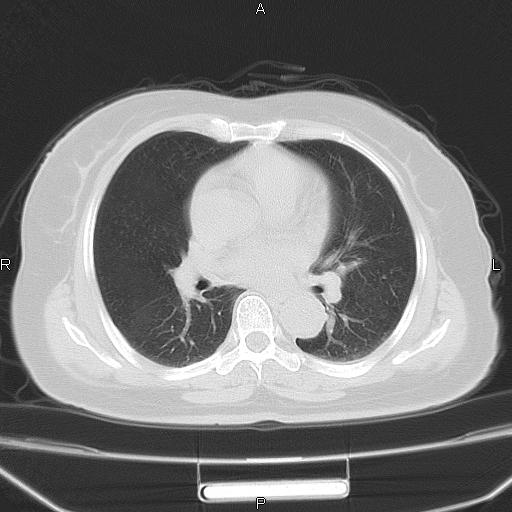

胸腺瘤

女、63Y 双眼睑下垂,早轻晚重。 胸腺瘤???

结果胸腺瘤